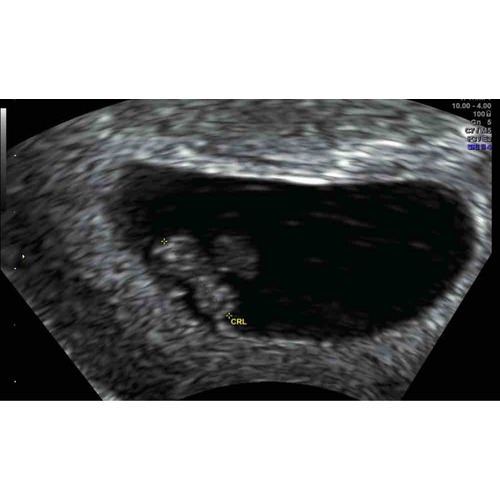

7+4🥰

Ze hebben het hartje niet laten horen omdat het blijkbaar slecht was, maar we zagen het hartje wel kloppen🥰